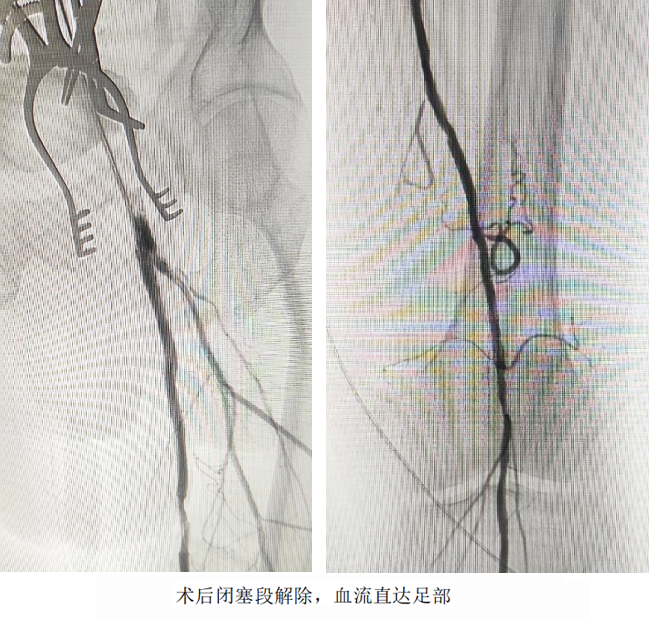

開放手術(shù)精準(zhǔn)“拆彈”,切開股動(dòng)脈,直視下完整剝脫致密鈣化斑塊,重建股總動(dòng)脈血流通道;介入技術(shù)微創(chuàng)“護(hù)航”,經(jīng)血管腔植入髂動(dòng)脈覆膜支架,快速隔絕夾層破口,防止主動(dòng)脈進(jìn)一步撕裂;利用長球囊對股淺動(dòng)脈閉塞段進(jìn)行“拓荒式”擴(kuò)張,并植入柔性支架重塑血管,確保血流直達(dá)足部。

術(shù)后次日,患者左下肢皮溫回升,疼痛消失;術(shù)后第3天,患者已實(shí)現(xiàn)獨(dú)立行走。家屬感激地說:“本來以為要坐輪椅了,沒想到還能重新站起來!”